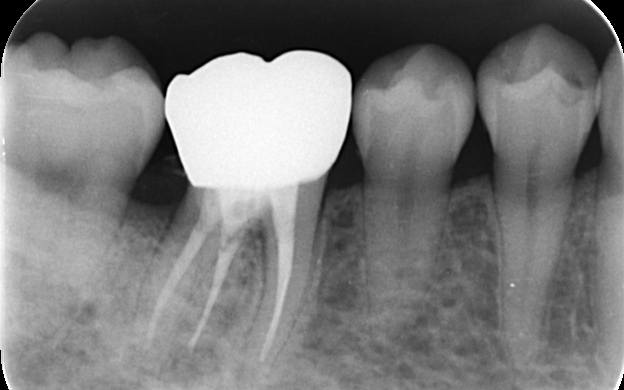

この治療は歯周病の再発リスクを大幅に減らし、長期間安定した状態を保つことができる方法です。 まずは歯周外科手術を行い、歯槽骨を必要な分だけ慎重に除去します。その後、健全な歯質が骨の縁から約3mm上に位置するよう精密に調整し、細菌の侵入を長期間防げる状態に整えました。 手術後は、歯茎と骨の状態が安定するまで経過観察を行い、十分に治癒したことが確認できたあと、顕微鏡を使用した「精密根管治療」を実施します。 続いて、歯の土台となるファイバー支台(ファイバーコア)を作製します。 土台が完成したあとは、被せ物を作製するための精密な型取りを行います。 最後に、完成したジルコニアセラミッククラウンを装着し、噛み合わせや見た目などに問題がないことを確認して、治療を終了しています。 |

精密根管治療を行いました。

精密な型取りを行いました。